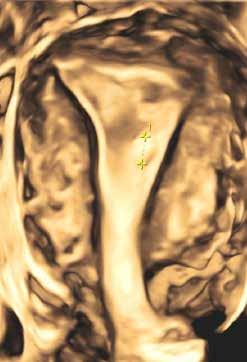

3D Sonographie

3D Sonographie mit einem kleinen Cavumpolyp und intakter Junztionszone.